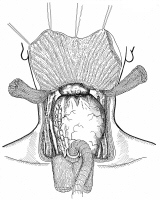

横隔膜切除後広背筋による再建

昔々、胸部外科の先生に頼まれて、描きました。